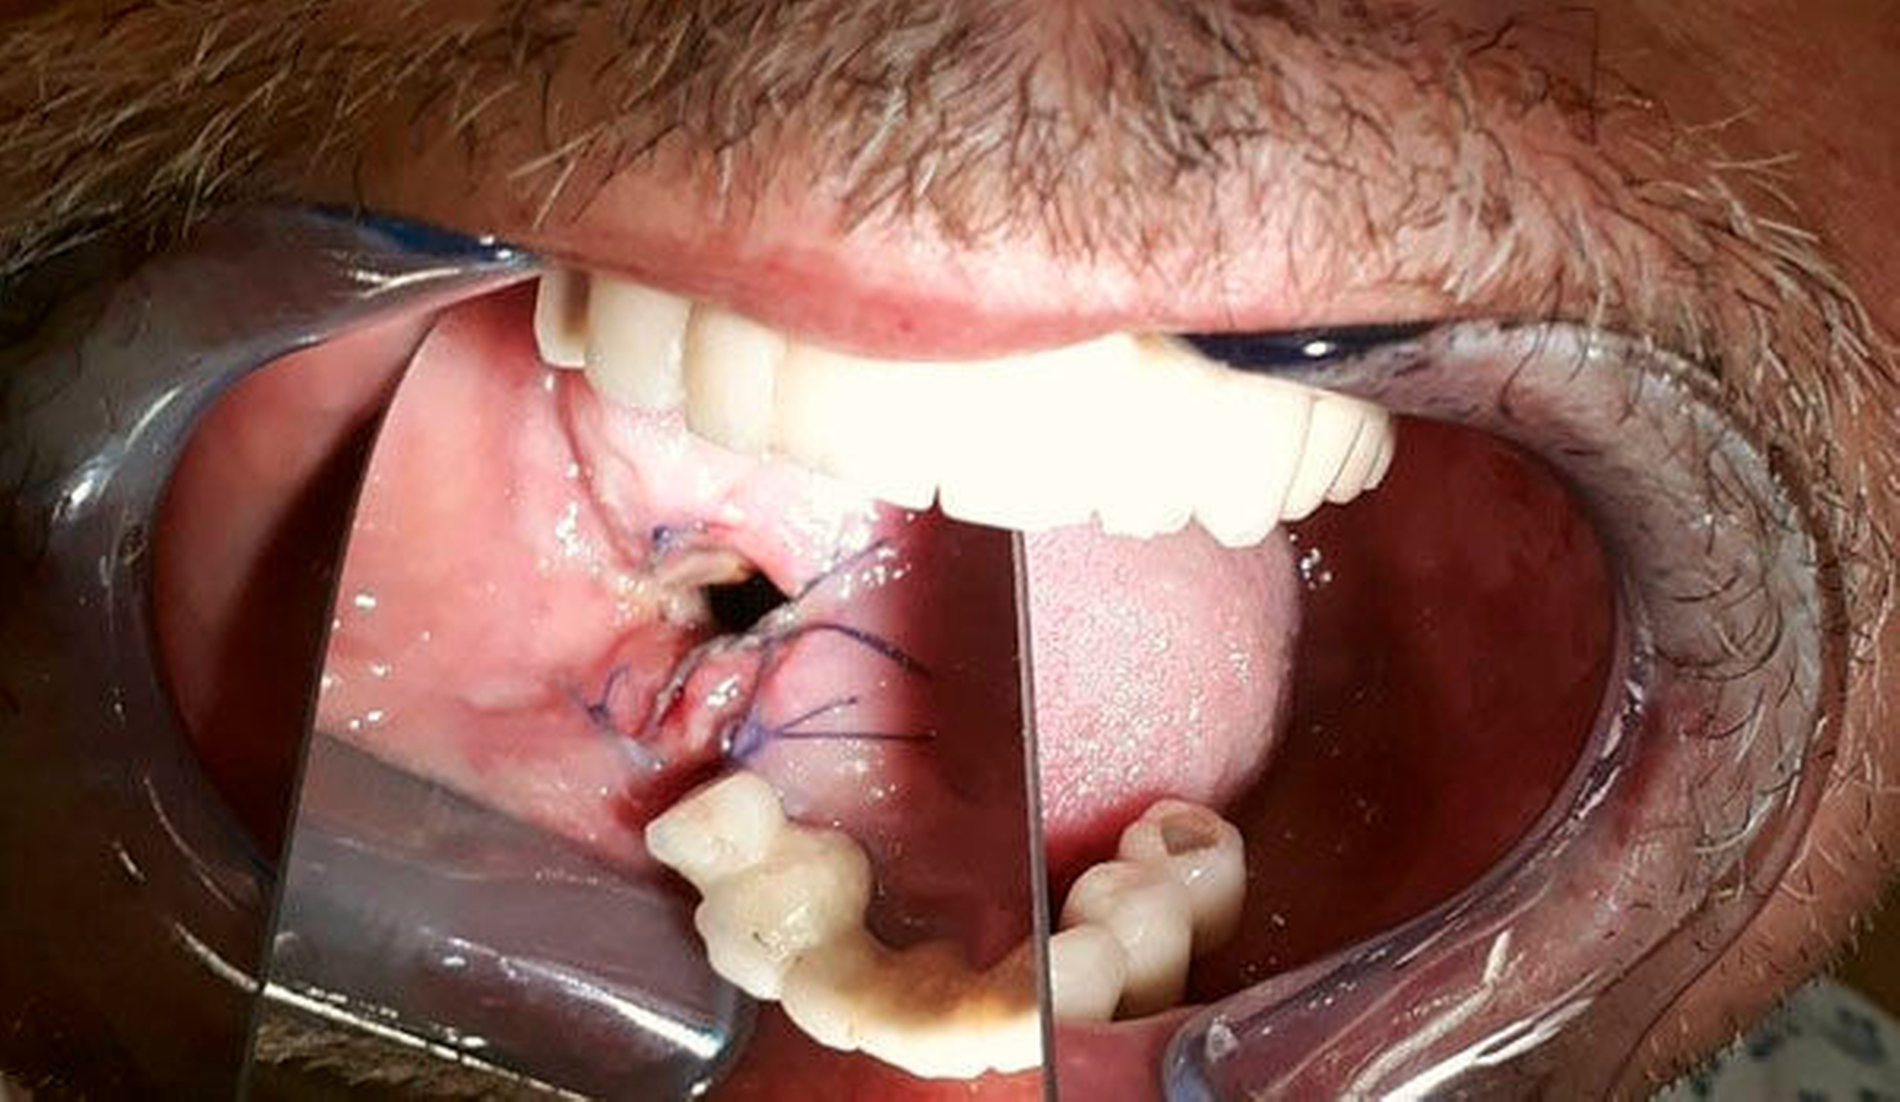

Intraoral zeigten sich implantatgetragene Kronen-Brückenkonstruktionen im Ober- und im Unterkiefer. Diese waren initial sowohl im Ober- als auch im Unterkiefer auf jeweils vier Implantaten befestigt. Im Bereich des rechten Oberkiefers zeigte sich in Regio 16 eine Mund-Antrum-Verbindung, die offenbar nach dem Versuch einer primären plastischen Deckung weiterbestand. Es bestand eine breite Dehiszenz bis ins Kieferhöhlenlumen hinein. An allen Implantaten zeigte sich eine chronische Periimplantitis mit ausgeprägtem Knochenabbau und freiliegenden oberen Gewindegängen.

Bei bereits reduziertem Visus und Einschränkung der Bulbusmotilität erfolgte nach ausführlicher Aufklärung des Patienten notfallmäßig die Inzision und Entlastung des Abszesses. Der Eingriff wurde noch am Aufnahmetag in der Notaufnahme unserer Mund-, Kiefer- und Gesichtschirurgischen Ambulanz in Lokalanästhesie von infraorbital anterior durchgeführt. Vom abfließenden Eiter wurde ein Abstrich genommen und zur mikrobiologischen Untersuchung geschickt. In den Inzisionsbereich wurde eine circa 4 cm lange, passive Kunststoffdrainage bis in die mittlere Orbita eingelegt und mit einer Naht fixiert. Der Patient wurde zur Überwachung und Weiterbehandlung stationär aufgenommen.

Die bestehende Mund-Antrum-Verbindung wurde nach Rücksprache mit dem Patienten am vierten stationären Tag in Lokalanästhesie geschlossen. Im Einzelnen wurden die Wundränder angefrischt, der Bichat‘sche Fettkörper dargestellt und mit Vicryl eingenäht, bevor der abschließende plastische Verschluss mit horizontalem Verschiebelappen und Periostschlitzung durchgeführt werden konnte.